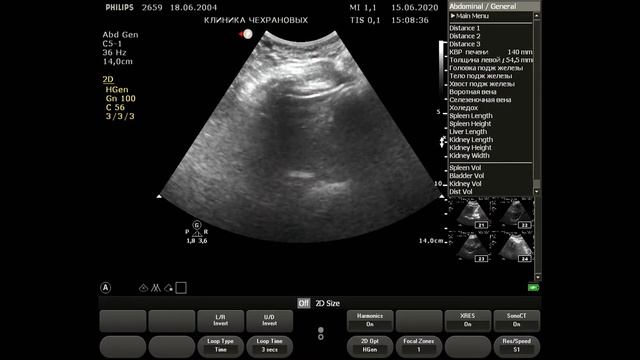

2020061211230694 УЗИ органов брюшной полости

Смотреть

Чехранов Андрей: Вези в УЗИ

2024-12-18 в 10:39:03